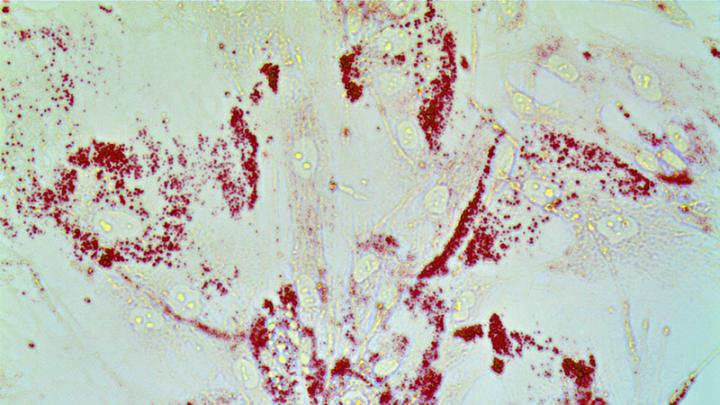

image: Cancer cells gobble up lipids. Prostate cells are stained with Oil-Red O to detect lipid droplets. Our work shows that redistribution of lipids from prostate cancer microenvironment triggers inflammation and drives prostate cancer metastasis.

In studies of human prostate cancer cell and stromal cell lines, when the lipid-regulating protein, called CAVIN1, was removed from stromal cells -- the connective tissue cells in and around tumors -- the cells no longer used the lipids. Instead, cancer cells feasted on lipids in the environment, using them as fuel, including to make hormones that feed the cancer.

In the human cell line experiments, when the researchers took CAVIN1 away from stromal cells called fibroblasts, the stromal cells no longer used the lipids, but the lipids remained in the environment, and to the researchers' surprise, they became a smorgasbord for the cancer cells. In every prostate cancer cell line tested, tumor cells universally had an appetite for the lipids, using them to fuel growth, strengthen the protective membrane around the cell, synthesize proteins and make testosterone to support the cancer's growth, says Jin-Yih Low, Ph.D., first author and a research fellow in the Department of Radiation Oncology and Molecular Radiation Sciences.

To confirm their findings, the researchers conducted similar experiments in mouse models, implanting the prostate cancer cells and stromal cells into the prostates of mice and comparing the behavior of tumors with and without CAVIN1 function in the stromal cells. Although the presence or loss of CAVIN1 did not impact the speed of tumor growth, lack of CAVIN1 caused the cancer to spread. All of the mice with tumors that did not express CAVIN1 had a twofold to fivefold increase in metastasis. The tumors also had a fortyfold to hundredfold increase in lipids and inflammatory cells.